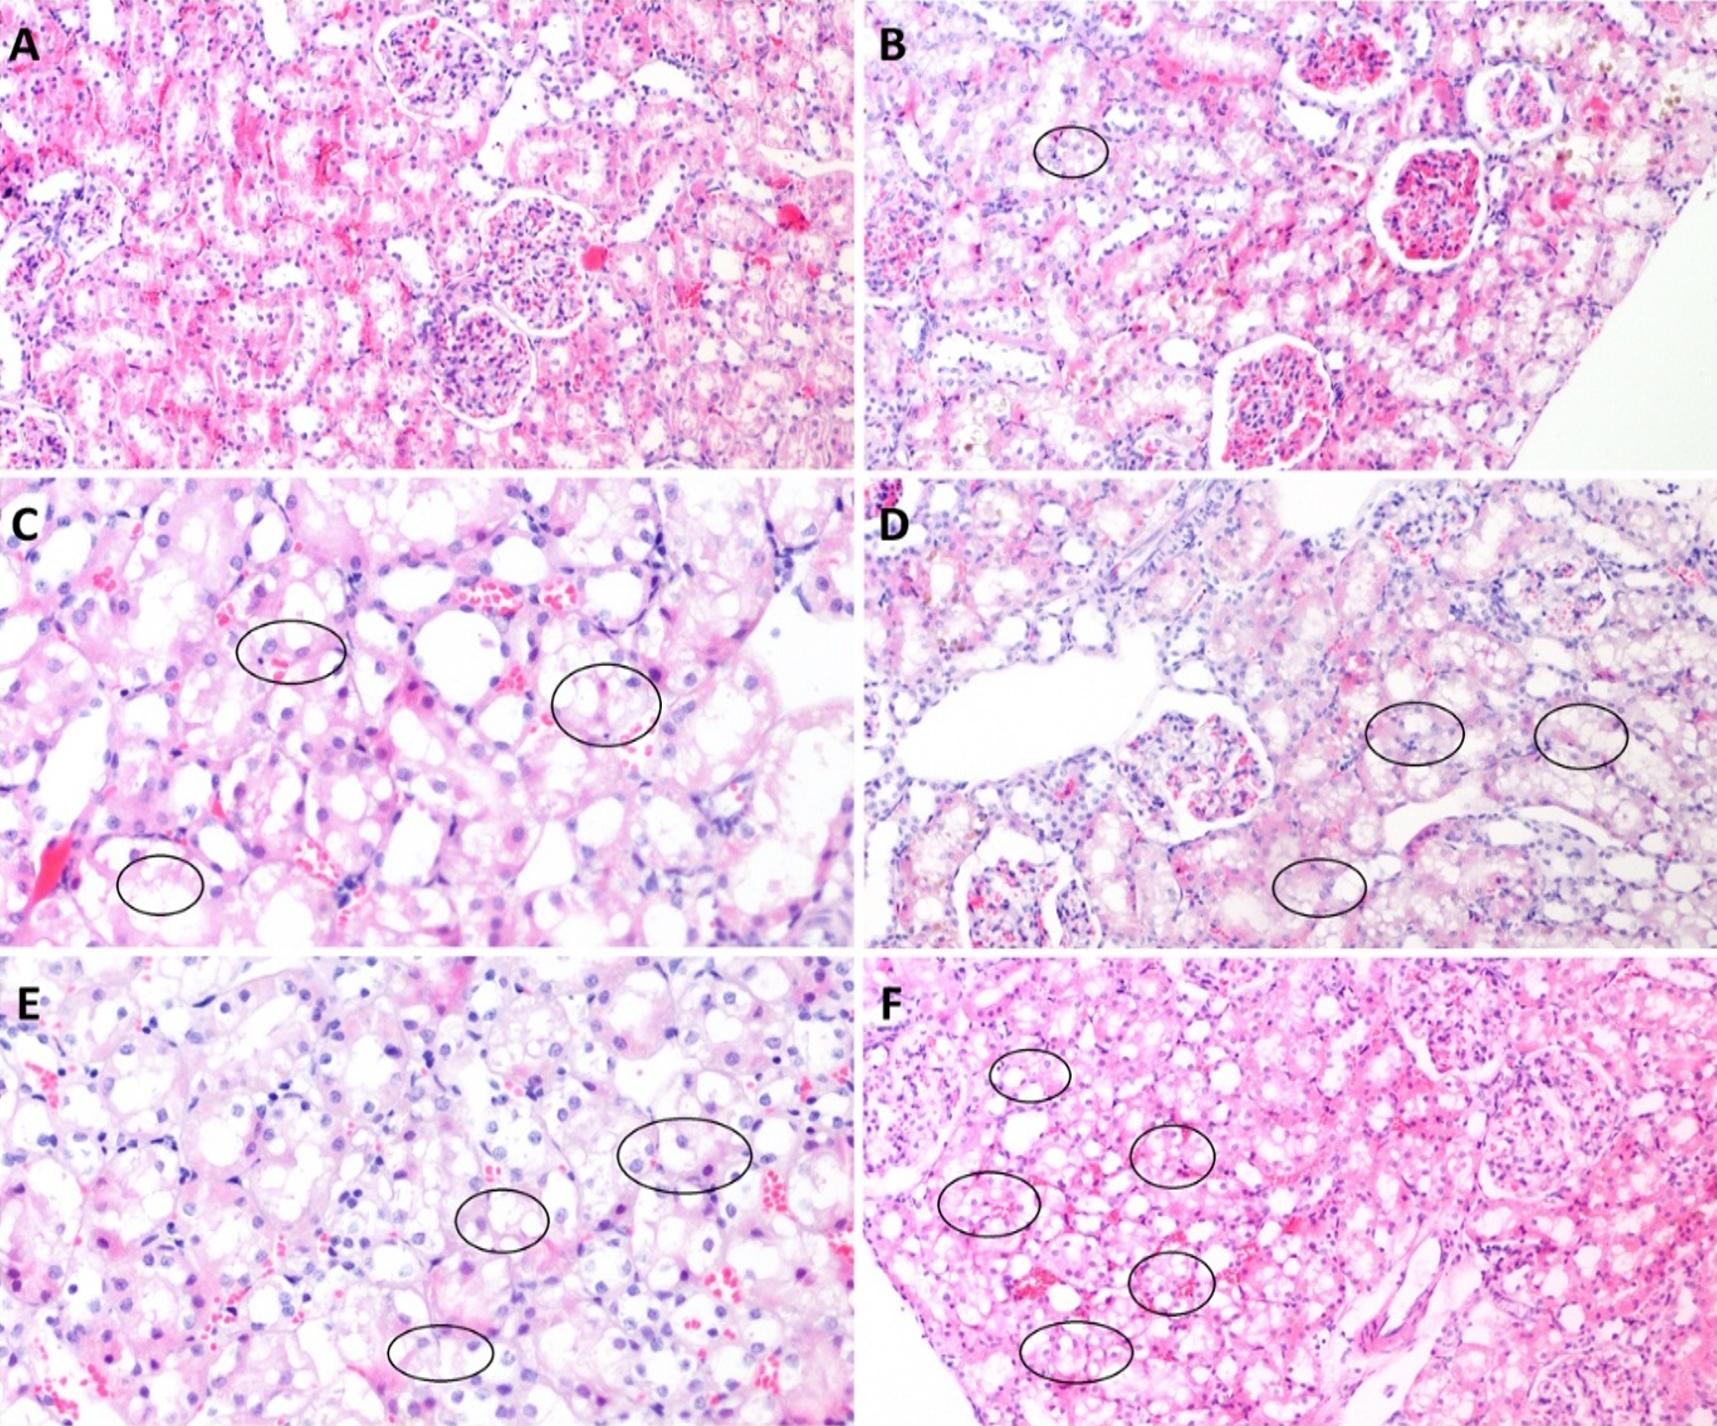

The rat kidneys fixed in 10% neutral buffered formalin solution for histopathological examination were subjected to standard tissue-processing steps in an automated device and embedded in paraffin blocks. Four µm-thick sections, on average, were cut from each block using a microtome and mounted on three slides, one of which was stained with Hematoxylin and Eosin (H&E), one with Periodic acid Schiff (PAS) for morphological assessment and one using the terminal deoxynucleotidyl transferase-mediated dUTP nick-end labeling technique (TUNEL), using ApopTag® Peroxidase In Situ Apoptosis Detection Kit for the assessment of apoptosis. The tissue sections prepared for examination were assessed by an experienced pathologist under a light microscope attached to a camera (Olympus BX53F; Tokyo, JAPAN) in a blind manner. Tubular necrosis and dilatation, vacuolar degeneration, the loss of the brush border and the cast development, as well as the ratio of findings in the percentage of tubules, were assessed to determine the tubular damage score. Using the Tubular Damage Scoring system, the damage grade is expressed at five levels: no damage=0, 1–10% = 1, 11–25% = 2, 26–50% = 3, 51–75% = 4, >75% = 5 (19,20). For the assessment of apoptosis, the number of TUNEL-positive nuclei in a total of 10 HPF was detected on the slides prepared using the TUNEL method.

The tissue samples were subjected to a histopathological examination and examined for the presence of tubular necrosis, loss of brush-border, cast formation, vacuolization, and tubular dilatation, in an evaluation of tubular damage. The loss of brush-border, tubular dilatation and vacuolization were the prominent findings in a histopathological examination following the CLP procedure (Figure 3-6). The Tubular Damage Score was used to grade the pathological damage (Table 2) and was significantly higher in Group 1 (at 3 hours after the CLP procedure) than in the sham group, with the highest damage score observed in Group 5 (Table 3). The percentage of apoptosis was similar across the groups when compared to the sham group (P>0.05), and there was no significant difference between the groups (P<0.05) (Table 3 and Figure 7).

Tubular dilatation and vacuolization, and the loss of the brush-border, to a lesser extent, were the most prominent alterations associated with AKI in the histopathological examination carried out within our polymicrobial sepsis model, created using the CLP method. In contrast, no apoptosis or necrosis, which are commonly reported as the most striking histopathological findings of SI-AKI in literature, were identified. In the present study, an analysis of the urinary CCAB revealed TIMP-2 to increase earlier, and to predict AKI with a higher sensitivity and specificity than IGFBP-7 (37,43). However, a cut-off value of 1.91(ng/ml)2 for the combined use of the two molecules showed the highest sensitivity and specificity in the early detection of SI-AKI. Although RRI predicted SI-AKI in the early period at the same time points as CCAB, RRI showed a higher sensitivity and specificity than the other two molecules.